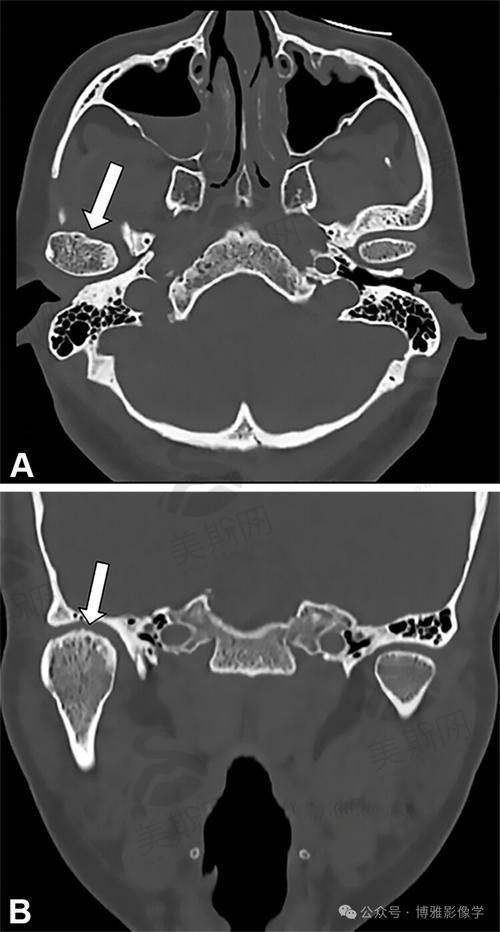

患者王先生(72岁)因重度牙周病导致全口牙齿脱落,佩戴活动假牙10年,因假牙松动无法咀嚼硬物,体重下降15斤。经易纯医生检查,确诊为牙槽骨重度吸收(上颚骨高度仅3mm),传统种植难度极大。易医生团队采用“All - on - 4即刻负重技术”,通过4颗倾斜种植体实现全口固定修复,手术耗时2小时,当天戴牙。术后1周复查,王先生已能正常进食米饭、苹果,3个月后骨结合稳定,CT显示种植体周围骨密度达85%。他反馈:“易医生不仅技术好,还耐心讲解每个步骤,现在吃饭香了,睡眠也改善了,真是救命恩人!”